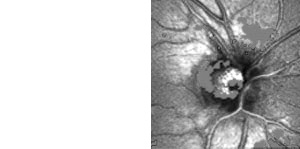

Heidelberger Retina Tomograph HRT

- Scanning - Laser-Tomographie

www.HeidelbergEngineering.com